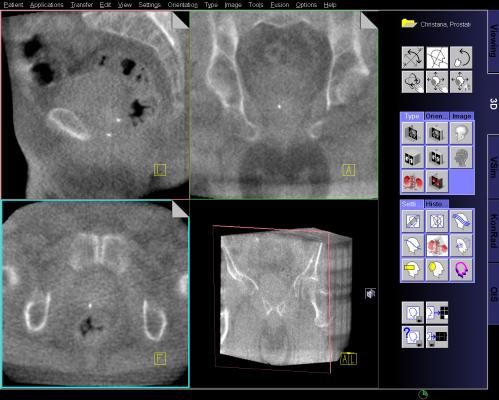

MRI Guided Biopsy: Dr. Samadi's Prostate Cancer Center uses the Uronav Fusion Biopsy System for magnetic resonance imaging (MRI)-guided biopsy. An MRI-ultrasound fusion biopsy involves taking an MRI and then fusing the data with real-time ultrasound images for guidance on biopsy procedures. The UroNav System combines electromagnetic tracking and navigation with an onboard computer and a real-time imaging interface in one mobile workstation. The MR/ultrasound fusion aligns and registers prior diagnostic MR images with real-time ultrasound images.